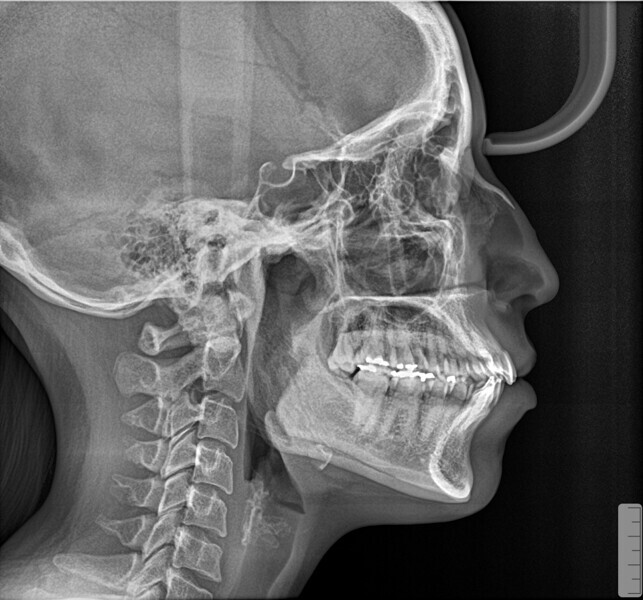

A 35-year-old female patient presented with crowding, muscle and joint pain, and headaches upon awakening. Examination found a skeletal Class I with crowding and bimaxillary protrusion. Facial examination showed a convex profile with protruded lips and a square face shape, intensified on smiling (Figs. 1–4). She reported bruxism, and bilateral masseteric hypertrophy was observed, but there was no alteration of the temporomandibular joints.

The objectives of the treatment included correcting the crowding, establishing a Class I occlusion, correcting the patient’s profile and reducing bruxism, along with its associated signs and symptoms. Orthodontic treatment using aligners was planned, together with the administration of botulinum toxin for the bruxism signs and symptoms and to improve the facial aesthetics.

Before the aligner treatment began, the maxillary and mandibular second premolars were extracted to create space. With orthodontic treatment, distalisation of the anterior teeth was achieved by employing maximum mandibular anchorage and moderate maxillary anchorage (Figs. 5–7). At the end of the treatment, a stable bilateral Class I occlusion had been achieved, as well as normal inclination and retrusion of the anterior teeth, consequently improving the profile (Figs. 8–10).